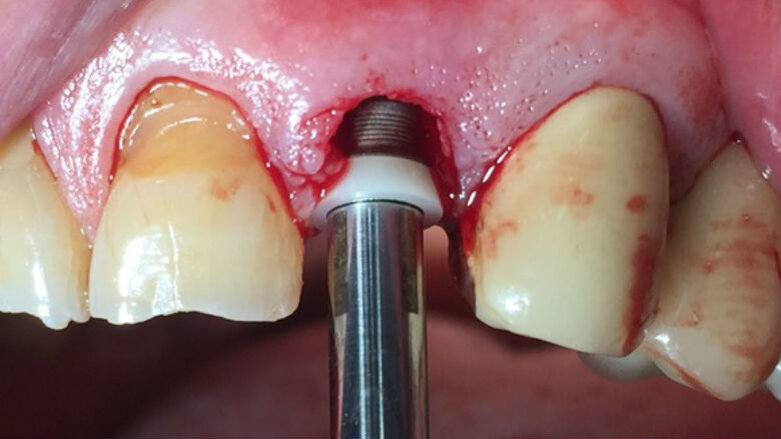

Le foto esplicative si riferiscono a un caso di riabilitazione estetica su paziente maschio di anni 76 con storia di bruxismo, in cui è stato inserito con carico immediato un impianto post estrattivo su 2.2 con mantenimento parziale del tavolato vestibolare nel rispetto del concetto di tunnel protesico di inserzione (Fig. 1). Il collare in zirconia è stato inserito per 1 mm sotto il tavolato e la porzione emergente ha la funzione di mantenimento a balcone del bombè connettivale e quindi di sostegno per i tessuti molli (Figg. 2, 3). La protesizzazione, avvenuta nelle 72 ore successive all’inserimento della fixture, è stata effettuata con impronta pick up e tecnica cementata con corona in PMMA eseguita al cad cam; l’angolo incisale della corona risultava assai smusso distalmente per agevolare i movimenti di svincolo in lateralità poiché il paziente è bruxista, come si evince dalle faccette di usura degli elementi naturali adiacenti (Fig. 4). Nonostante il biotipo gengivale sottile già nelle prime fasi dal carico si può notare l’effetto biomimetico del collare in zirconia e l’accettazione paraimplantare sul versante estetico.